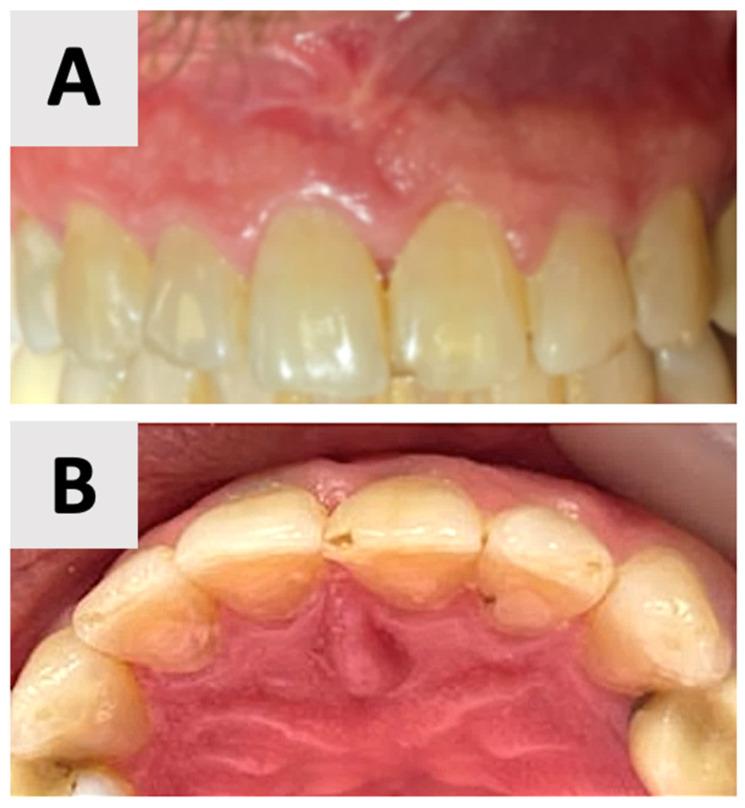

A 35-year-old male patient presented with a large periapical cystic lesion in the maxillary anterior region. Treatment involved marsupialization followed by cyst enucleation and GBR using a resorbable magnesium membrane and bovine xenograft. The magnesium membrane served as a structural support to bridge the bony discontinuity in the palatal bone. Cone-beam computed tomography (CBCT) was used for diagnosis, treatment planning, and follow-up assessments. At 16 months post-treatment, CBCT imaging revealed significant bone regeneration, with restoration of the palatal contour and cortication of the palatal wall. Clinical examination showed asymptomatic teeth with normal mobility and optimal soft tissue healing.

一名35岁男性患者上颌前部出现一个大的根尖囊性病变。治疗包括袋形术,随后进行囊肿摘除术,并使用可吸收镁膜和牛异种移植物进行引导骨再生。镁膜作为一种结构支撑物,用于桥接腭骨的骨不连续处。锥形束计算机断层扫描(CBCT)用于诊断、治疗计划制定和随访评估。治疗后16个月,CBCT成像显示骨再生显著,腭轮廓恢复,腭壁皮质化。临床检查显示牙齿无症状,松动度正常,软组织愈合良好。